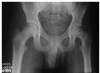

Quais os achados de imagem da DLCP?

AP e Lauenstein (posição de rã): diminuição epifisária com aumento do espaço articular, hiperdensidade, fratura subcondral (crescente). Pode haver fragmentação e cistos metafisários.